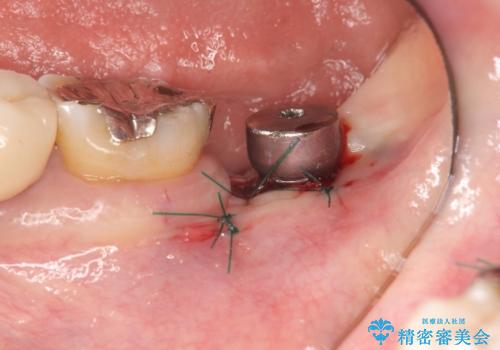

- 50万円(ストローマンインプラント・骨造成・チタンカスタムアバットメント・メタルボンド)費用は治療当時の料金となります

良好なインプラントの植立を行うためには、十分な骨量があることが必須条件です。

術前、歯の破折により大きな骨の吸収が認められていたため骨量を十分に回復するために抜歯と同時に歯槽堤保存術を行い十分な骨量の回復をすることができました。